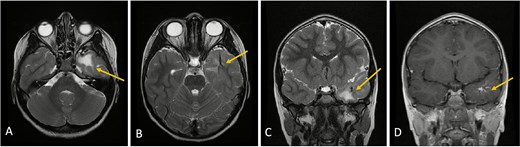

Axial lower cut (A)/axial higher cut (B)/coronal (C) T2-weighted MRI of the brain shows stable findings of a prominent area of T2 hyperintensity in the white matter of the left anterior temporal lobe, adjacent to the known DVA (arrow), which is clearly delineated on the contrasted sequence (D).

Clinical and radiological follow-up was advised. Serial MRIs at two and four months demonstrated no change in venous morphology or white matter signal. The patient’s clinical course remained uneventful, with no neurological deficits noted (Fig. 3).